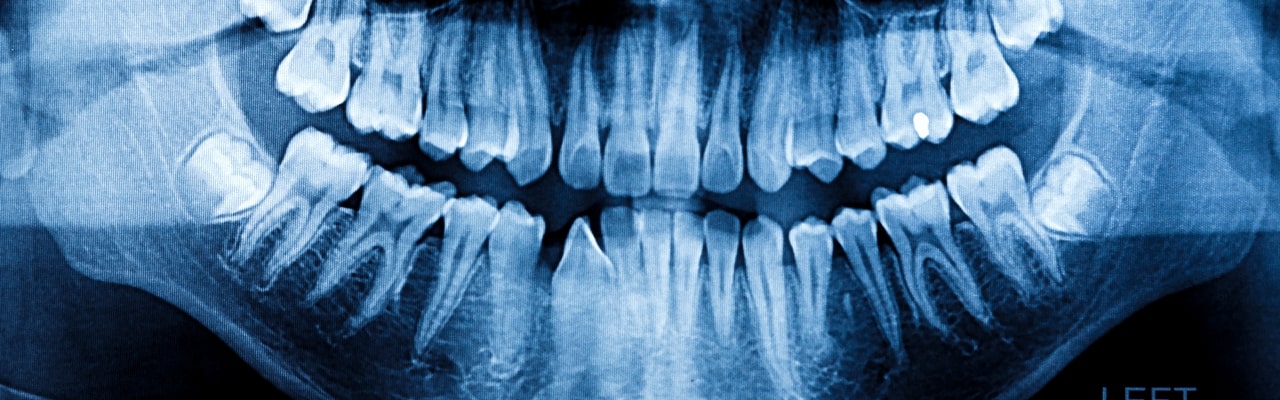

The teeth are strong, but they are still prone to fractures, cracks, and breaks. Sometimes fractures are fairly painless, but if the crack extends down into the root, it is likely that the pain will be extreme. Fractures, cracks, and breaks can take several different forms, but are generally caused by trauma, grinding, and biting. If a tooth has been fractured or cracked, there is no alternative but to schedule an appointment as quickly as possible.

The nature of the break or fracture will limit what we are able to do. If a fracture or crack extends into the root, root canal therapy is often the most effective way to retain the tooth. In the case of a complete break, your dentist will usually affix the fragment back onto the tooth as a temporary measure.